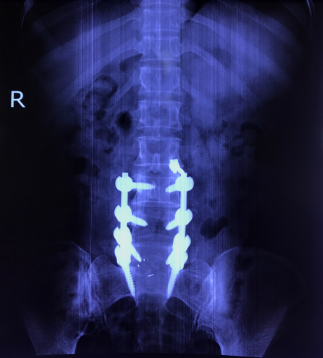

Hình ảnh: X Quang bệnh nhân sau phẫu thuật hàn xương, nắn chỉnh cột sống